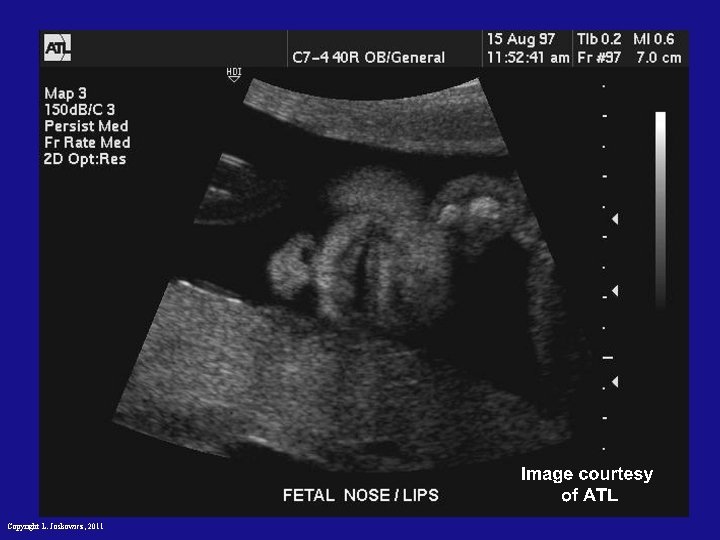

Ultrasound imaging Copyright L. Joskowicz, 2011

Ultrasound: principle • Probe sends high-frequency (1 – 5 Mhz) sound waves into body • Sound waves travel into tissue and get reflected by boundaries • Reflected waves recorded by probe • Time of flight gives spatial info of the boundaries • Frequency of signal depends on a tradeoff resolution versus attenuation Copyright L. Joskowicz, 2011

Ultrasound imaging: characteristics • No radiation • Poor resolution (1 mm) nonuniform, distortion, noise • Low penetration properties • One 2 D slice or several slices (2. 5 D) • Relatively cheap and easy to use • Preoperative and intraoperative use Copyright L. Joskowicz, 2011